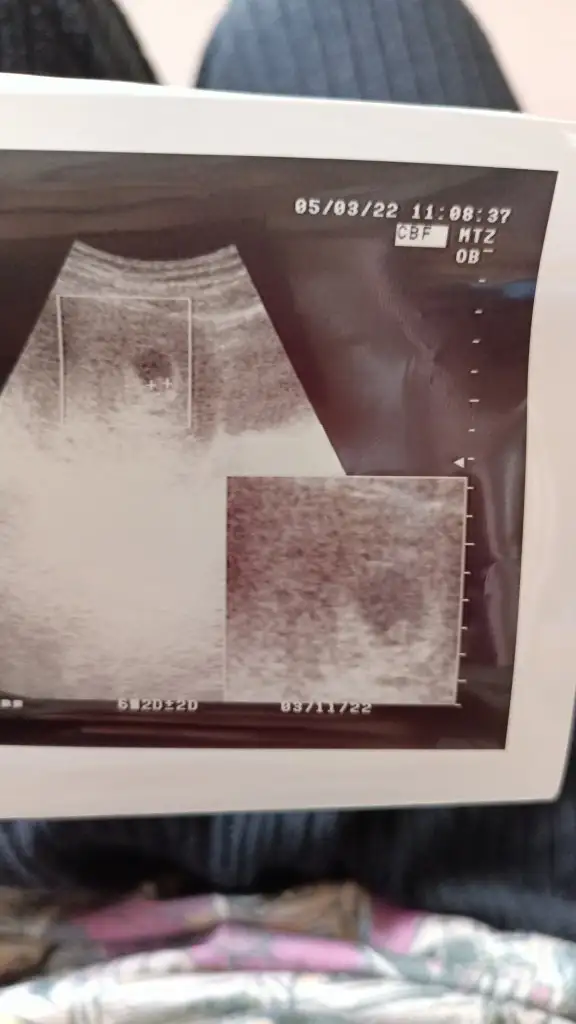

Kiza benziyo ama pek emin degilimEki Görüntüle 3073009 bizde 7 haftalığız karından tahminde bulunabilir misiniz

ErkekMerhabalaarr benim için de tahminde bulunur musunuzultrason ölçümüne göre 5+6, vajinal ultrason Eki Görüntüle 3072069